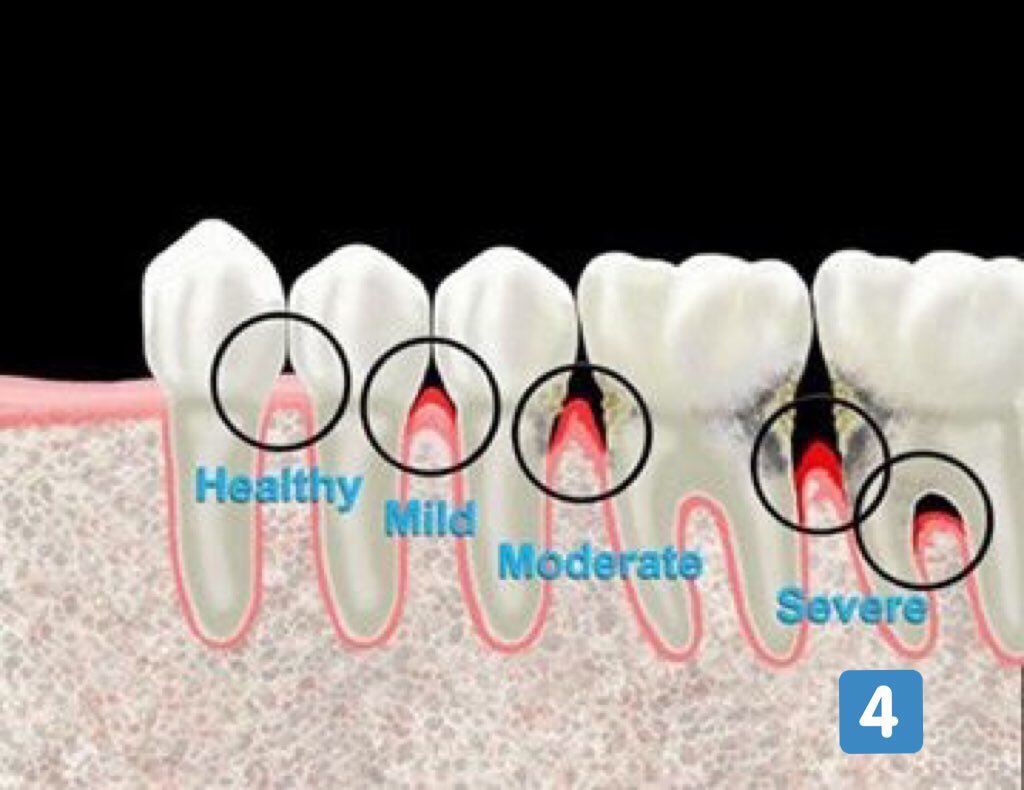

المرحلة المتقدمة من التهاب اللثة (المرحلة ٤):

-ألم ونزف

-حركة واضحة ومؤلمة عند المضغ

-رائحة كريهة ومزعجة

-سقوط الأسنان بدون التعرض لضربات أو حوادث

-العلاج قد يكون غير ممكن 💔